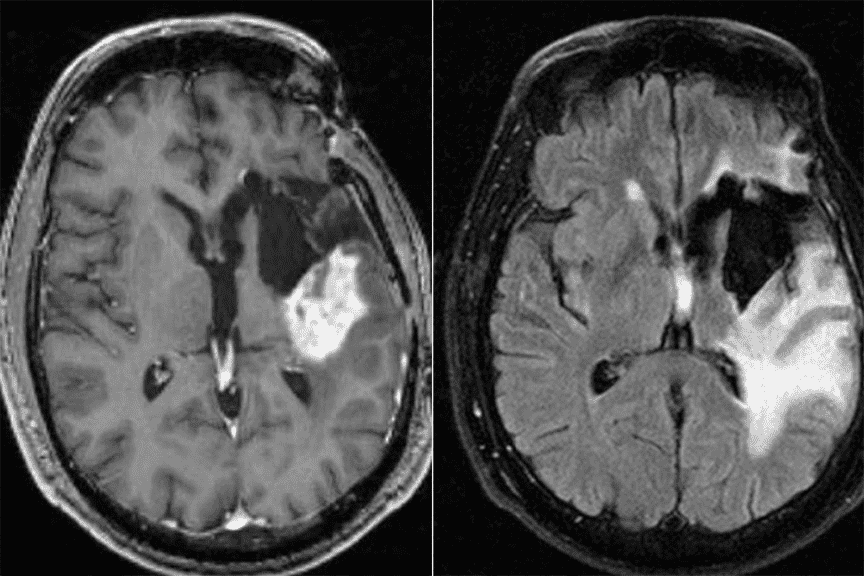

伦敦癌症研究所开创的光激活技术使癌细胞在黑暗中发光,使外科医生能够去除更多的肿瘤,同时在手术完成后消除任何残留细胞。这项尖端技术甚至暴露了最小的癌细胞,爱游戏ayx体育使外科医生更容易将其删除。

胶质母细胞瘤是最严重的脑癌类型之一,并且正在对患有该疾病的小鼠进行新的疗法。

新型摄影疗法的试验还表明,该治疗触发了一种免疫反应,可以在将来靶向癌细胞的免疫系统,这表明它可以防止胶质母细胞瘤在手术后返回。研究人员现在还正在研究儿童癌症神经母细胞瘤的新治疗方法。

“我们的研究表明,使用荧光标记物,杂物蛋白和近红外光的新型摄影疗法治疗可以鉴定和治疗小鼠中剩余的胶质母细胞瘤细胞。将来,我们希望这种方法也可以用来治疗人类胶质母细胞瘤和可能的其他癌症。”他补充说。